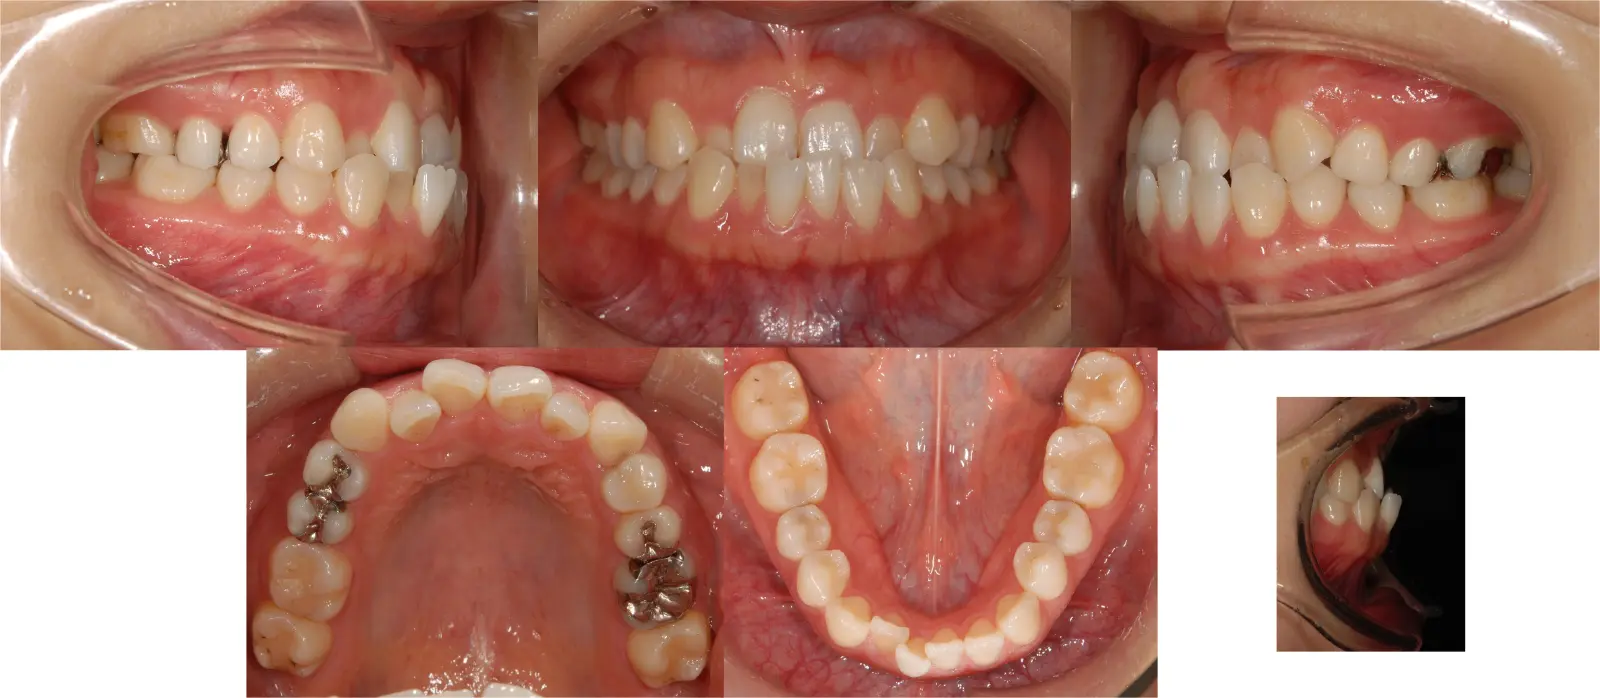

軽度叢生を伴う骨格性反対咬合

- 主訴

受け口

- 年齢

60代

- 治療期間

1年9ヶ月

- 治療回数

20回

- 治療に用いた主な装置

カスタムメイド型マルチブラケットタイプのデジタル矯正装置(インシグニア)

- 治療費

700,000円(税別)、調整料5,000円(税別)

※伊那分院にて治療

- 抜歯部位

非抜歯による